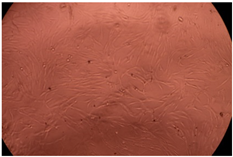

| Sample | Micrographs | ||

|---|---|---|---|

| 24 h | 48 h | ||

| Control |  |  | |

| F127 | 10 µg/mL |  |  |

| 50 µg/mL |  |  | |

| 100 µg/mL |  |  | |

| 200 µg/mL |  |  | |

| F127/PA = 10/1 (g/g) | 10 µg/mL |  |  |

| 50 µg/mL |  |  | |

| 100 µg/mL |  |  | |

| 200 µg/mL |  |  | |